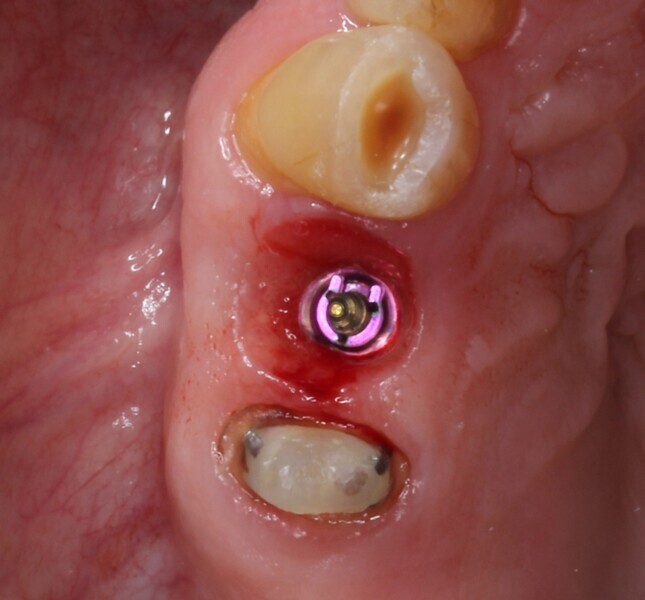

Tooth #14 was deemed unrestorable, and so it was decided to extract the tooth (Figs. 3 & 4), wait for bony healing and replace it with an implant with a provisional restoration. During the healing process, endodontic therapy would be performed on tooth #15. After bony integration, implant #14 would be restored with a screw-retained direct-to-implant zirconia crown, and tooth #15 would also be restored with a complete zirconia crown. A deliberately lighter shade would be chosen, factoring in the patient’s long-term desire to improve the colour of his teeth.

Fig. 4: Post-extraction site.

The fit of the surgical guide was confirmed, and the patient was anaesthetised locally (Fig. 15). A small full-thickness flap was raised, and a guided osteotomy was performed. The implant was inserted to a 45 N cm torque. The prefabricated two-piece provisional restoration was torqued in to 15 N cm and was confirmed to be out of occlusion. Two 4-0 PROLENE sutures (Ethicon) were used to close the flap (Figs. 16–19).